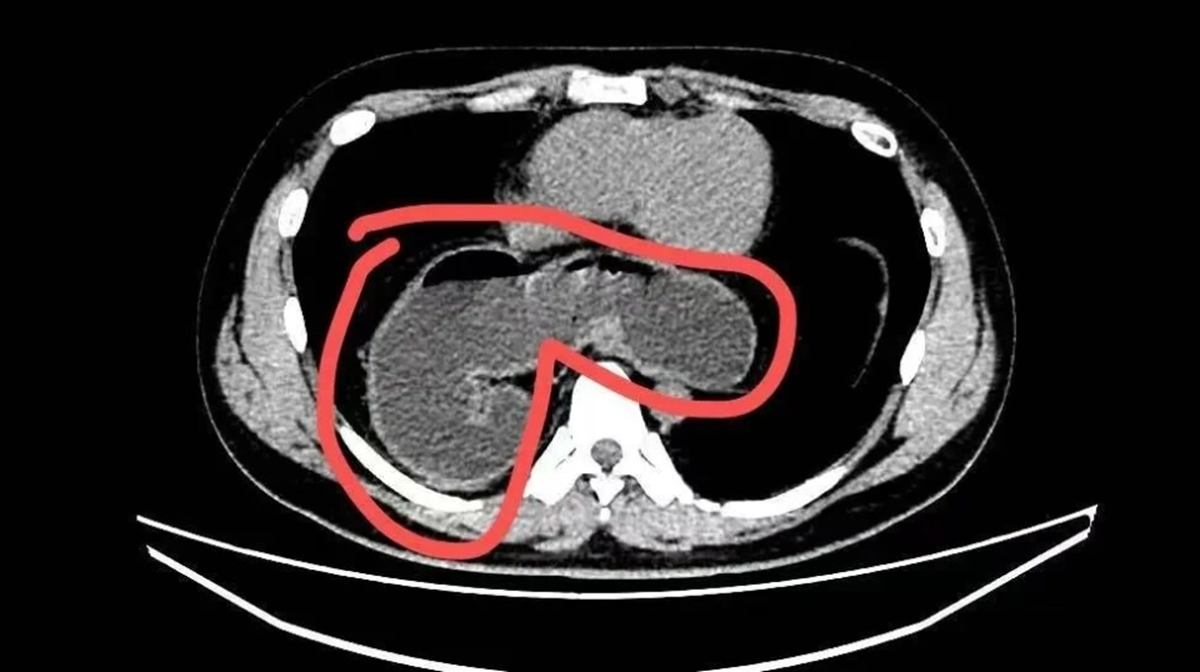

Mãi đến tháng 10 năm ngoái, do ho kéo dài kèm viêm phổi dai dẳng không khỏi, anh được chụp CT phổi. Kết quả khiến cả bệnh nhân lẫn gia đình sững sờ: một phần dạ dày đã “chạy” qua lỗ thực quản lên lồng ngực . Nội soi sau đó xác định anh mắc thoát vị khe thực quản kèm viêm thực quản trào ngược và xoắn dạ dày . Rất may, anh được phẫu thuật xâm lấn tối thiểu và xuất viện chỉ sau 3 ngày.

Theo bác sĩ, thoát vị khe thực quản xảy ra khi lỗ tự nhiên trên cơ hoành - nơi thực quản đi từ ngực xuống bụng - bị giãn rộng bất thường. Khi “cánh cửa” này lỏng ra, dạ dày, thậm chí cả ruột hoặc lách, có thể bị đẩy ngược lên khoang ngực. Hệ quả là axit dạ dày dễ trào ngược gây nóng rát, ợ chua, khó nuốt, đau ngực; nặng hơn có thể dẫn đến xoắn dạ dày, tắc nghẽn, không ăn uống được.